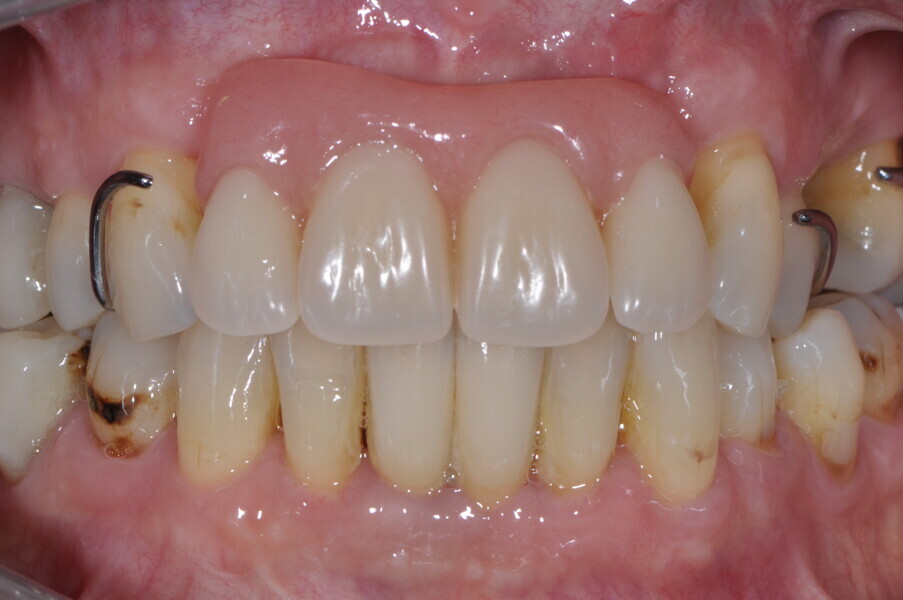

A 62-year-old male patient was referred to my practice for implant planning and treatment in the maxillary anterior region. The teeth in the maxillary anterior region had all undergone endodontic therapy, and teeth #11-22 had received crowns owing to an accident that had occurred 30 years before. The patient reported pain and was conscious that tooth #21 was mobile (Figs. 1a & b).

Fig. 1b: Initial situation.